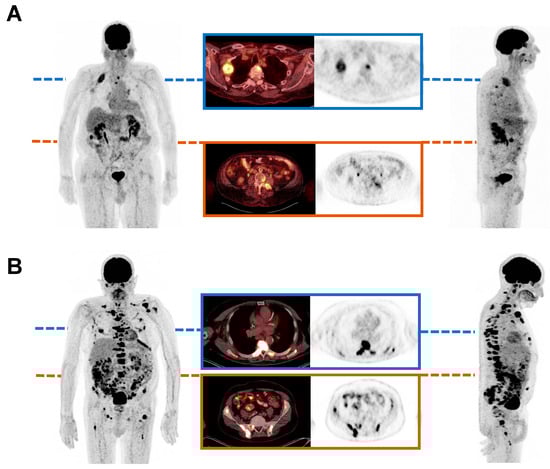

2.4. Evaluation of Predictive Biomarkers

- Rosar, F.; Burgard, C.; David, S.; Marlowe, R.J.; Bartholomä, M.; Maus, S.; Petto, S.; Khreish, F.; Schaefer-Schuler, A.; Ezziddin, S. Dual FDG/PSMA PET Imaging to Predict Lesion-Based Progression of mCRPC During PSMA-RLT. Sci. Rep. 2024, 14, 11271. [Google Scholar] [CrossRef] [PubMed]